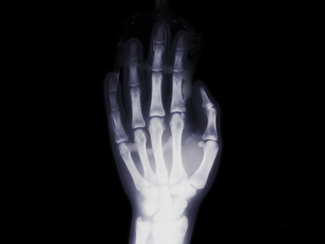

In der Röntgendiagnostik werden die drei Techniken Röntgenaufnahmen, Röntgendurchleuchtungen und Computertomographien (CT) unterschieden.

Die Röntgendiagnostik wird vom Arzt eingesetzt, wenn mit anderen Verfahren wie Labor-, Ultraschall- oder endoskopischen Untersuchungen keine eindeutige Diagnose zu erhalten ist. Mit der Röntgendiagnostik wird oft erst die Diagnose ermöglicht oder erhärtet beziehungsweise der Befund präzisiert.